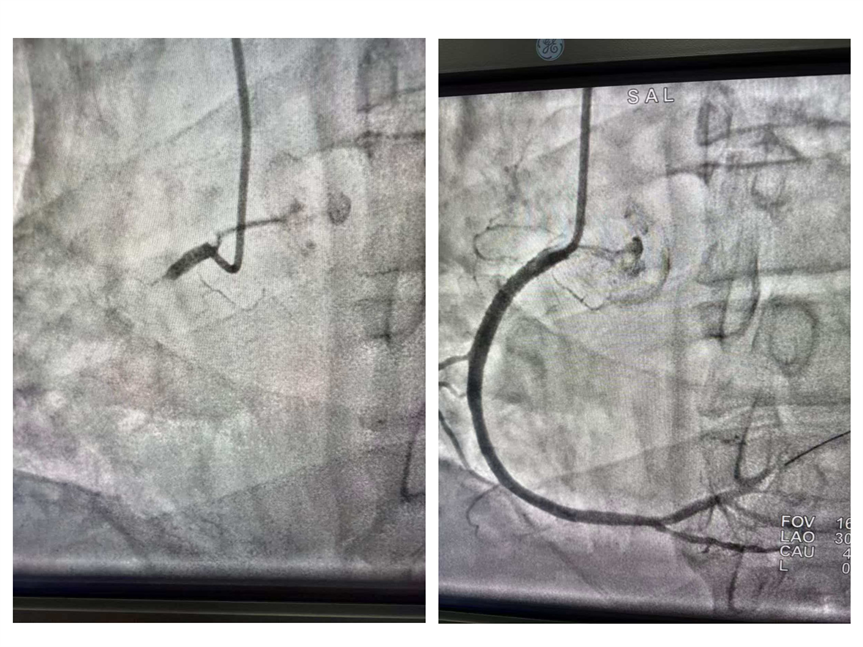

考虑到患者病情进展迅猛,随时可能出现心跳骤停,胸痛中心潘洪涛主任当机立断:“跳过常规术前等待,直接推送导管室开展急诊PCI!”在导管室内,治疗团队争分夺秒开展手术。通过选择性冠状动脉造影术,清晰显示患者冠状动脉左主干及三支血管均存在严重狭窄,且血管内形成8cm长的血栓,堵塞血管导致心肌严重缺血。面对复杂凶险的病情,团队精准施策,依次开展经皮冠状动脉腔内成形术扩张狭窄血管、冠状动脉内血栓抽吸术清除块状血栓、冠状动脉内溶栓术溶解残余血栓,最终成功植入冠状动脉内药物洗脱支架,实现血管血运重建。

(术前术后造影对比图)